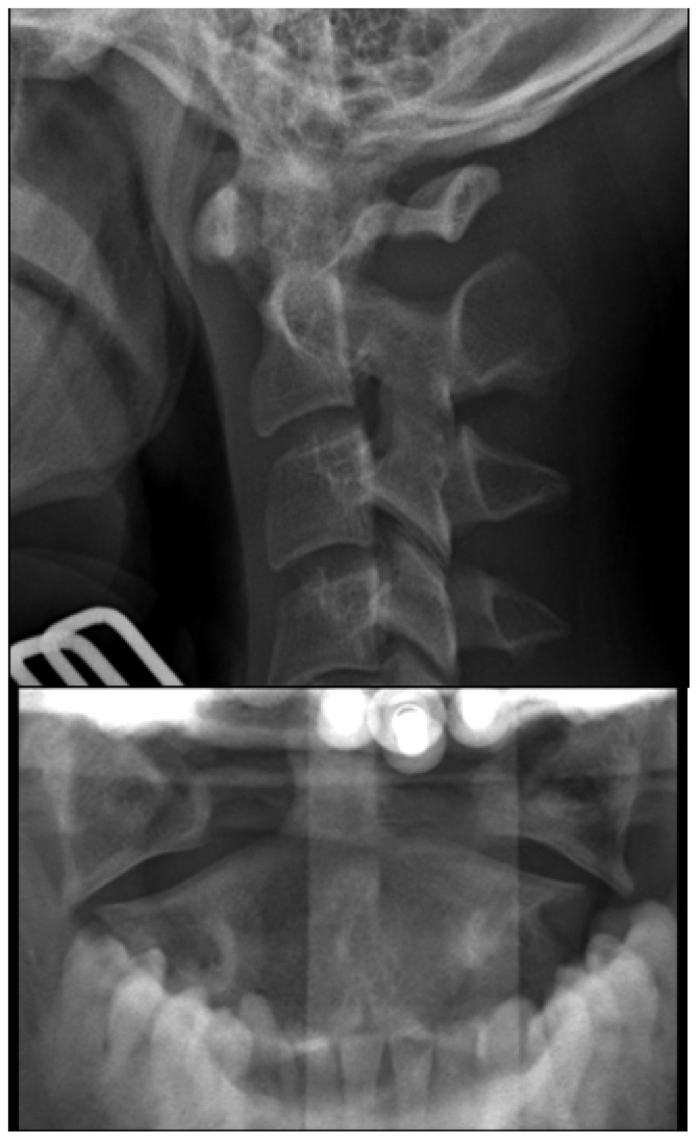

C-spine Radiographs

• Why are children more prone to high cervical spine injuries?

• Name 7 normal variants of pediatric cervical spine

A

• By 8 to 9 years of age, cervical spine reaches adult proportions

• Cervical spine injuries in children usually occur high - from the occiput to C3 vertebra

• Fulcrum of motion in children is at the C2-C3 level rather than at the C5-C6 level in adults

• Owing to hypermobility of the c-spine because of ligamentous laxity, shallow and angled facet joints, anteriorly wedged vertebrae, and underdeveloped spinous processes

• Weak neck muscles, underdeveloped odontoid process, and large head also contribute to instability of the c-spine

• For screening, obtain lateral, AP, and odontoid views of the cervical spine

Approach

• Every lateral c-spine view should visualize at least the top of T1, of not, may need swimmer’s

• Lateral

• Upper C-spine

• Atlantodens interval (< 5 mm)

• Spinolaminar line should intersect with opisthion

• Relationship between basion and odontoid and posterior vertebral line for atlantooccipital dislocation - should be less than 12 mm (?), head usually dislocated anterior on cervical spine

• Look at odontoid

• C2 on C3 subluxation, C2 pedicles

Normal Pediatric Variants:

• ADI = atlantodens interval or distance between anterior wall of the dens (odontoid process) and posterior wall of the atlas’ anterior ring

• In children less than 5 mm is normal

• If greater than 5 mm, suspect ligamentous disruption

• Pseudo spread of the atlas on the axis can be seen on the odontoid view

• Pseudo Jefferson fracture

• Up to 6 mm of displacement of lateral masses relative to the dens can be seen commonly in patients under 4 years and may be seen up to 7 years of age

• Pseudo subluxation of C2 on C3

• C2 on C3 and to a lesser extent C3 on C4 can have physiologic displacement

• Check posterior cervical line (line between anterior aspects of spinous processes of C1, 2, and 3) - should line up within 1 mm

• If the posterior cervical line does not overlap anterior aspect of spinous process of C2 by more than 2 mm, true injury is present

• Abnormal posterior cervical line suspect occult hangman fracture of C2

• Absence of lordosis may be seen up to 16 years

• Posterior intraspinous distance should not be more than 1.5 the distance of the levels above and below the level in question

• In children, flexion can cause fanning of the C1 and C2 spinous processes (tight ligamentous connection of C1 to skull base)

• Anterior wedging of up to 3 mm of the vertebral bodies

• Can be marked at C3

• Normal physeal plates - expected location, smooth and regular, subchondral sclerotic lines

• vs fracture - occur at any location, irregular lines, no sclerosis

• Prevertebral space of less than 6 mm in children is normal

• Widening of prevertebral space can be due to expiration - if widened, repeat in slight extention and inspiration